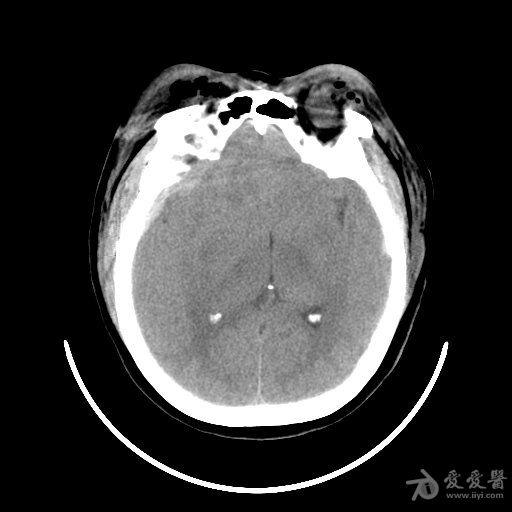

颞窝硬膜外血肿,开不开?何时开?

图片尺寸512x512